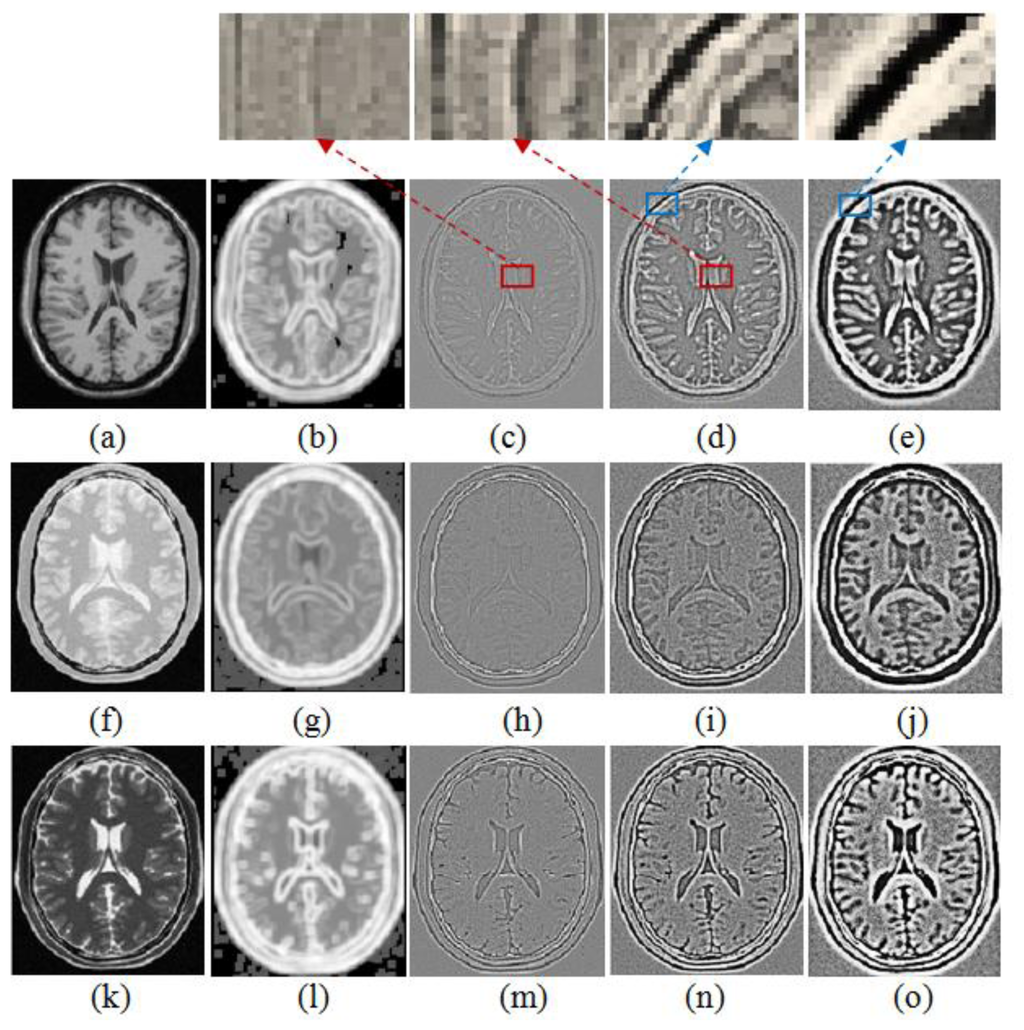

To demonstrate the performance of the WLD with different R and its advantage over the entropy image for structural representation, the WLD and the entropy image for deformed T1, PD and original T2 weighted MR images are shown in Figure 4. The comparison between Figure 4(b) and Figure 4(c–e) shows that the detail information in the entropy image of T1 weighted MR images is blurrier than that in the WLD, which indicates that the WLD can provide better structural representation than the entropy image for registration. It should be noted that there exist the black squares and dots in Figure 4(b) because the considered pixel is set to be zero when the minimum intensity is equal to the maximum one in the image patch centered at this pixel. Meanwhile, it is easy to understand that the performance of the WLD changes with different R.

From Figure 4(c–e), (h–j) and (m–o), we can see that the WLD with a small R (e.g., R = 1) generates relatively weak but thin edges and thus facilitates the accurate localization of relatively strong edges. By comparison, the WLD with a larger R (e.g., R = 2) produces thicker but stronger edges and thus assists with detecting the weak edges while a much larger R (e.g., R = 3) results in poor edge localization. The zooming of features marked with the red square in Figure 4(c–d) and those marked with the blue square in Figure 4(d–e) can further illustrate the above characteristics. Obviously, the combination of multiple selected R for the WLD produces “multi-granuality” features especially in regions with rich textures and discontinuities. Therefore, using the various radii in the WLD is preferable to using a single radius for the effective structural representation of medical images with complicated features. Based on the above analysis, we use the WLD with R = 1 and R = 2 for structural representation of images.